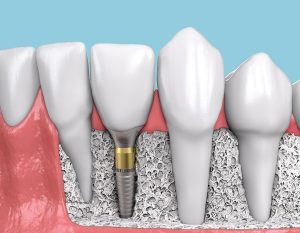

Un implante dental es una raíz artificial de titanio que colocamos en los huesos alveolares de los maxilares, superior o inferior (mandíbula) y que se adapta completamente con los tejidos de la boca. El objetivo y finalidad de los implantes es servir de soporte a una corona o prótesis que sustituirá a piezas dentales que hayamos perdido o que estén muy deterioradas.

Fase protésica

En algunas ocasiones colocamos la prótesis provisional el mismo día que el implante siempre que esto no comprometa el procedimiento. Posteriormente, una vez que el implante se haya integrado en el hueso, colocaremos la prótesis definitiva.